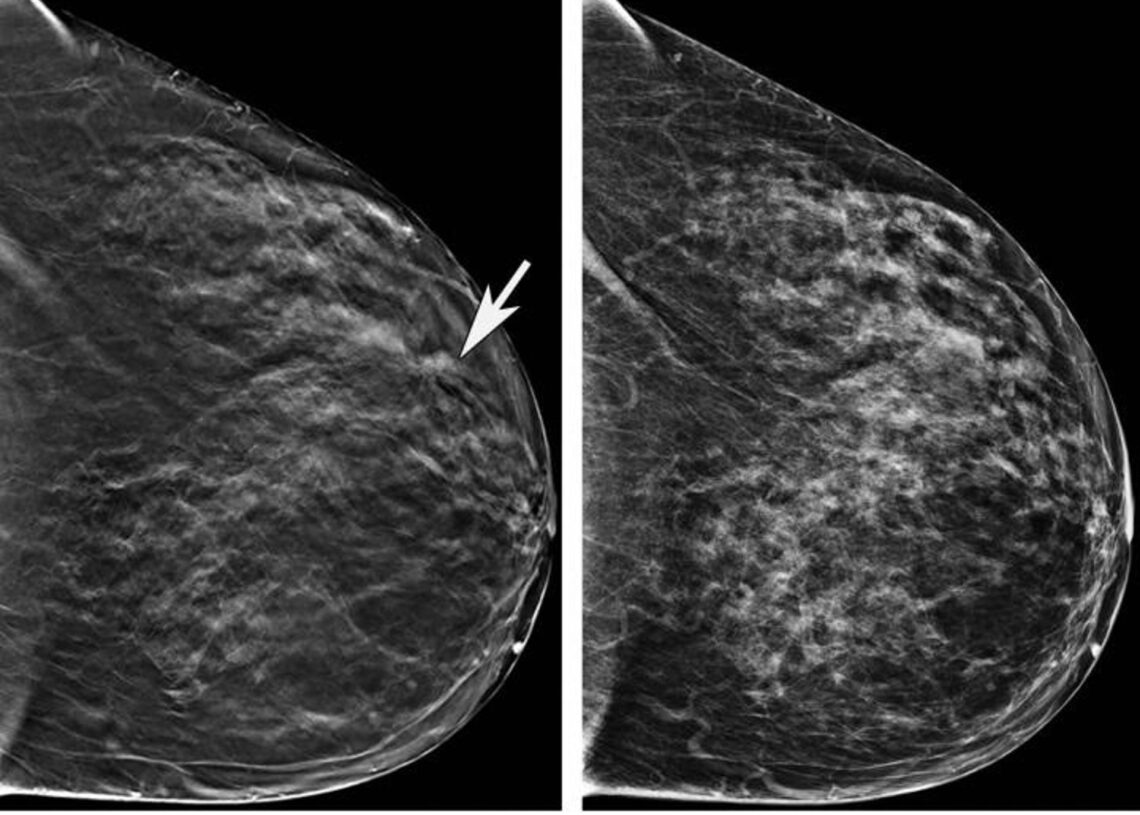

Almudena Quintana Morgado, directora general Asistencial del Servicio Madrileño de Salud (Sermas), ha asegurado la eficiencia del Programa de Detección Precoz del Cáncer de Mama (DEPRECAM) en Madrid, destacando que no hay listas de espera estructurales y que el tiempo medio de espera es de 34 días para realizar una mamografía, garantizando además que todas las pacientes son informadas sobre los resultados de sus pruebas.

Según la directora, los resultados de las pruebas son comunicados en menos de 30 días, y en caso de resultados sospechosos, la derivación al hospital se produce en aproximadamente 13,7 días. Ha destacado la transparencia y la seguridad del programa al asegurar que todas las mujeres reciben información detallada sobre el estado de su mamografía.

Durante 2023, el programa ha detectado 2.576 casos sospechosos de cáncer, requiriendo pruebas adicionales para confirmar el diagnóstico. Además, la tasa de detección de cáncer está en 5,4 casos por cada mil mujeres examinadas, con un alto porcentaje de detección en estadios iniciales, lo que facilita tratamientos menos invasivos y mejora las tasas de curación.